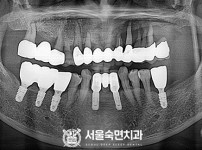

임플란트-전후사진1